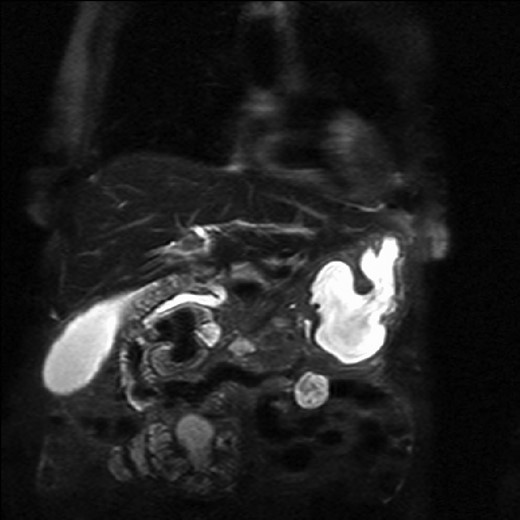

The patient underwent an MRCP which demonstrated mild distension of the gallbladder with several calculi. There was intra- and extra-hepatic biliary dilatation to the level of the ampulla. A very large fluid and air filled periampullary duodenal diverticulum measuring ~8 cm in the long axis was also noted (Figs 1–3). This finding was unchanged compared to a CT study from 6 months previously. The CBD was dilated to the level of this diverticulum and the cause of the patient’s biliary dilatation and obstruction. Interestingly, an unusual appearance to the kidneys was recorded with multiple microcystic changes in both kidneys, which is typically reported in patients with lithium induced renal disease. A gastroduodenoscopy revealed a large periduodenal diverticulum in D2 (Fig. 4).

Magnetic resonance imaging with a giant duodenal diverticulum.